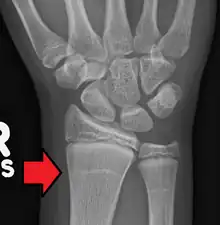

Growth arrest lines in a child with an underlying bone disease

Growth arrest lines, also known as Harris lines, are lines of increased bone density that represent the position of the growth plate at the time of insult to the organism and formed on long bones due to growth arrest. They are only visible by radiograph or in cross-section. The age at which the lines were formed can be estimated from a radiograph. Harris lines are often discussed as a result of juvenile malnutrition, disease or trauma. Other studies suggest a reconsideration of Harris lines as more of a result of normal growth and growth spurts, rather than a pure outcome of nutritional or pathologic stress.[1] The lines are named after Henry Albert Harris (1886–1968), professor of anatomy at the University of Cambridge.[2]

Particularly, deficiencies in protein and vitamins, which lead to delayed longitudinal bone growth, can result in the formation of Harris lines.[3] During the process of endochondral bone growth, the cessation of osteoblastic activity results in the deposition of a thin layer of bone beneath the cartilage cap, potentially forming Harris lines.[4][5] Subsequent recovery, necessary for the restoration of osteoblastic activity, is also implicated in Harris line formation.[6] When matured cartilage cells reactivate, bone growth resumes, causing a thickening of the bony stratum. Therefore, complete recovery from periods of chronic illness or malnutrition also manifests as transverse lines on radiographs. Lines tend to be thicker with prolonged and severe malnutrition. Harris line formation typically peaks in long bones around 2–3 years after birth and becomes rare until adulthood after the age of 5. Additionally, Harris lines occur more frequently in boys than in girls.[7]